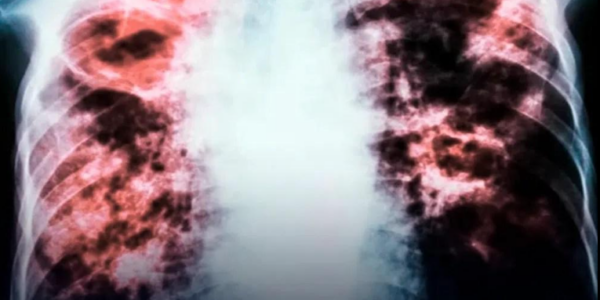

Frau behauptet: „Tod ist eine Illusion“

Symbolfoto: Shutterstock Eine Frau, die acht Minuten lang klinisch tot war, beschrieb ein außergewöhnliches Nahtoderlebnis, das, wie sie sagt, alles veränderte, was sie über das Leben und das Danach glaubte. Brianna Lafferty, 33, kämpfte lange mit Myoklonus-Dystonie, einer seltenen neurologischen…